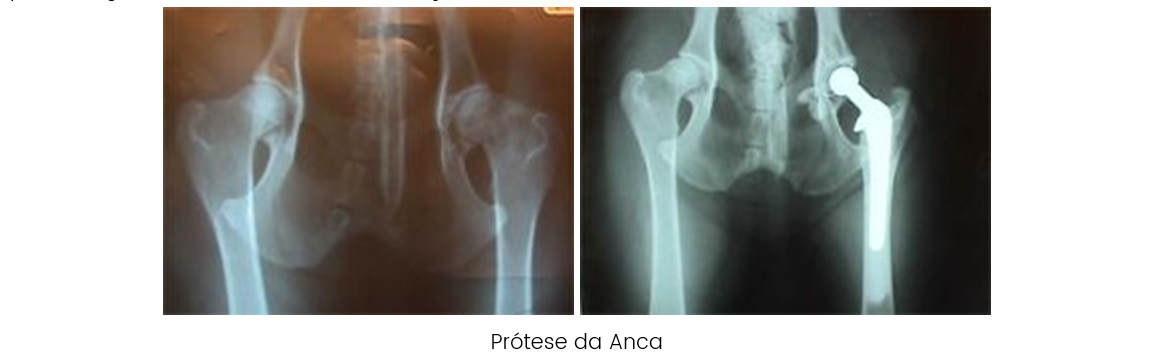

PRÓTESE TOTAL DA ANCA: A substituição da articulação coxo femoral em animais com osteoartrose por uma prótese é uma técnica cada vez mais utilizada. Geralmente utilizam-se próteses cimentadas com uma percentagem de êxito 60 a 100% em função da técnica utilizada.